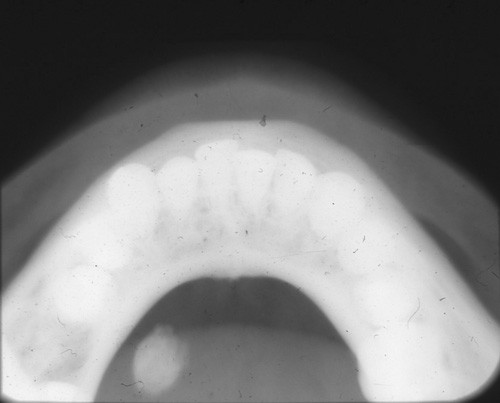

4. (Select ONE OR MORE correct answers)

The radiograph shows evidence of